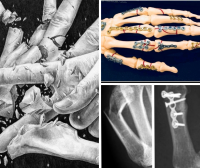

Chirurgia mâinii

Intervenții chirurgicale la nivelul mâinii pentru redobândirea funcționalității sau a aspectului cosmetic după traumatisme, infecții locale, modificări reumatice, deformări congenitale sau dobândite, Maladia Dupuytren, Sindrom canal carpian, tumori.